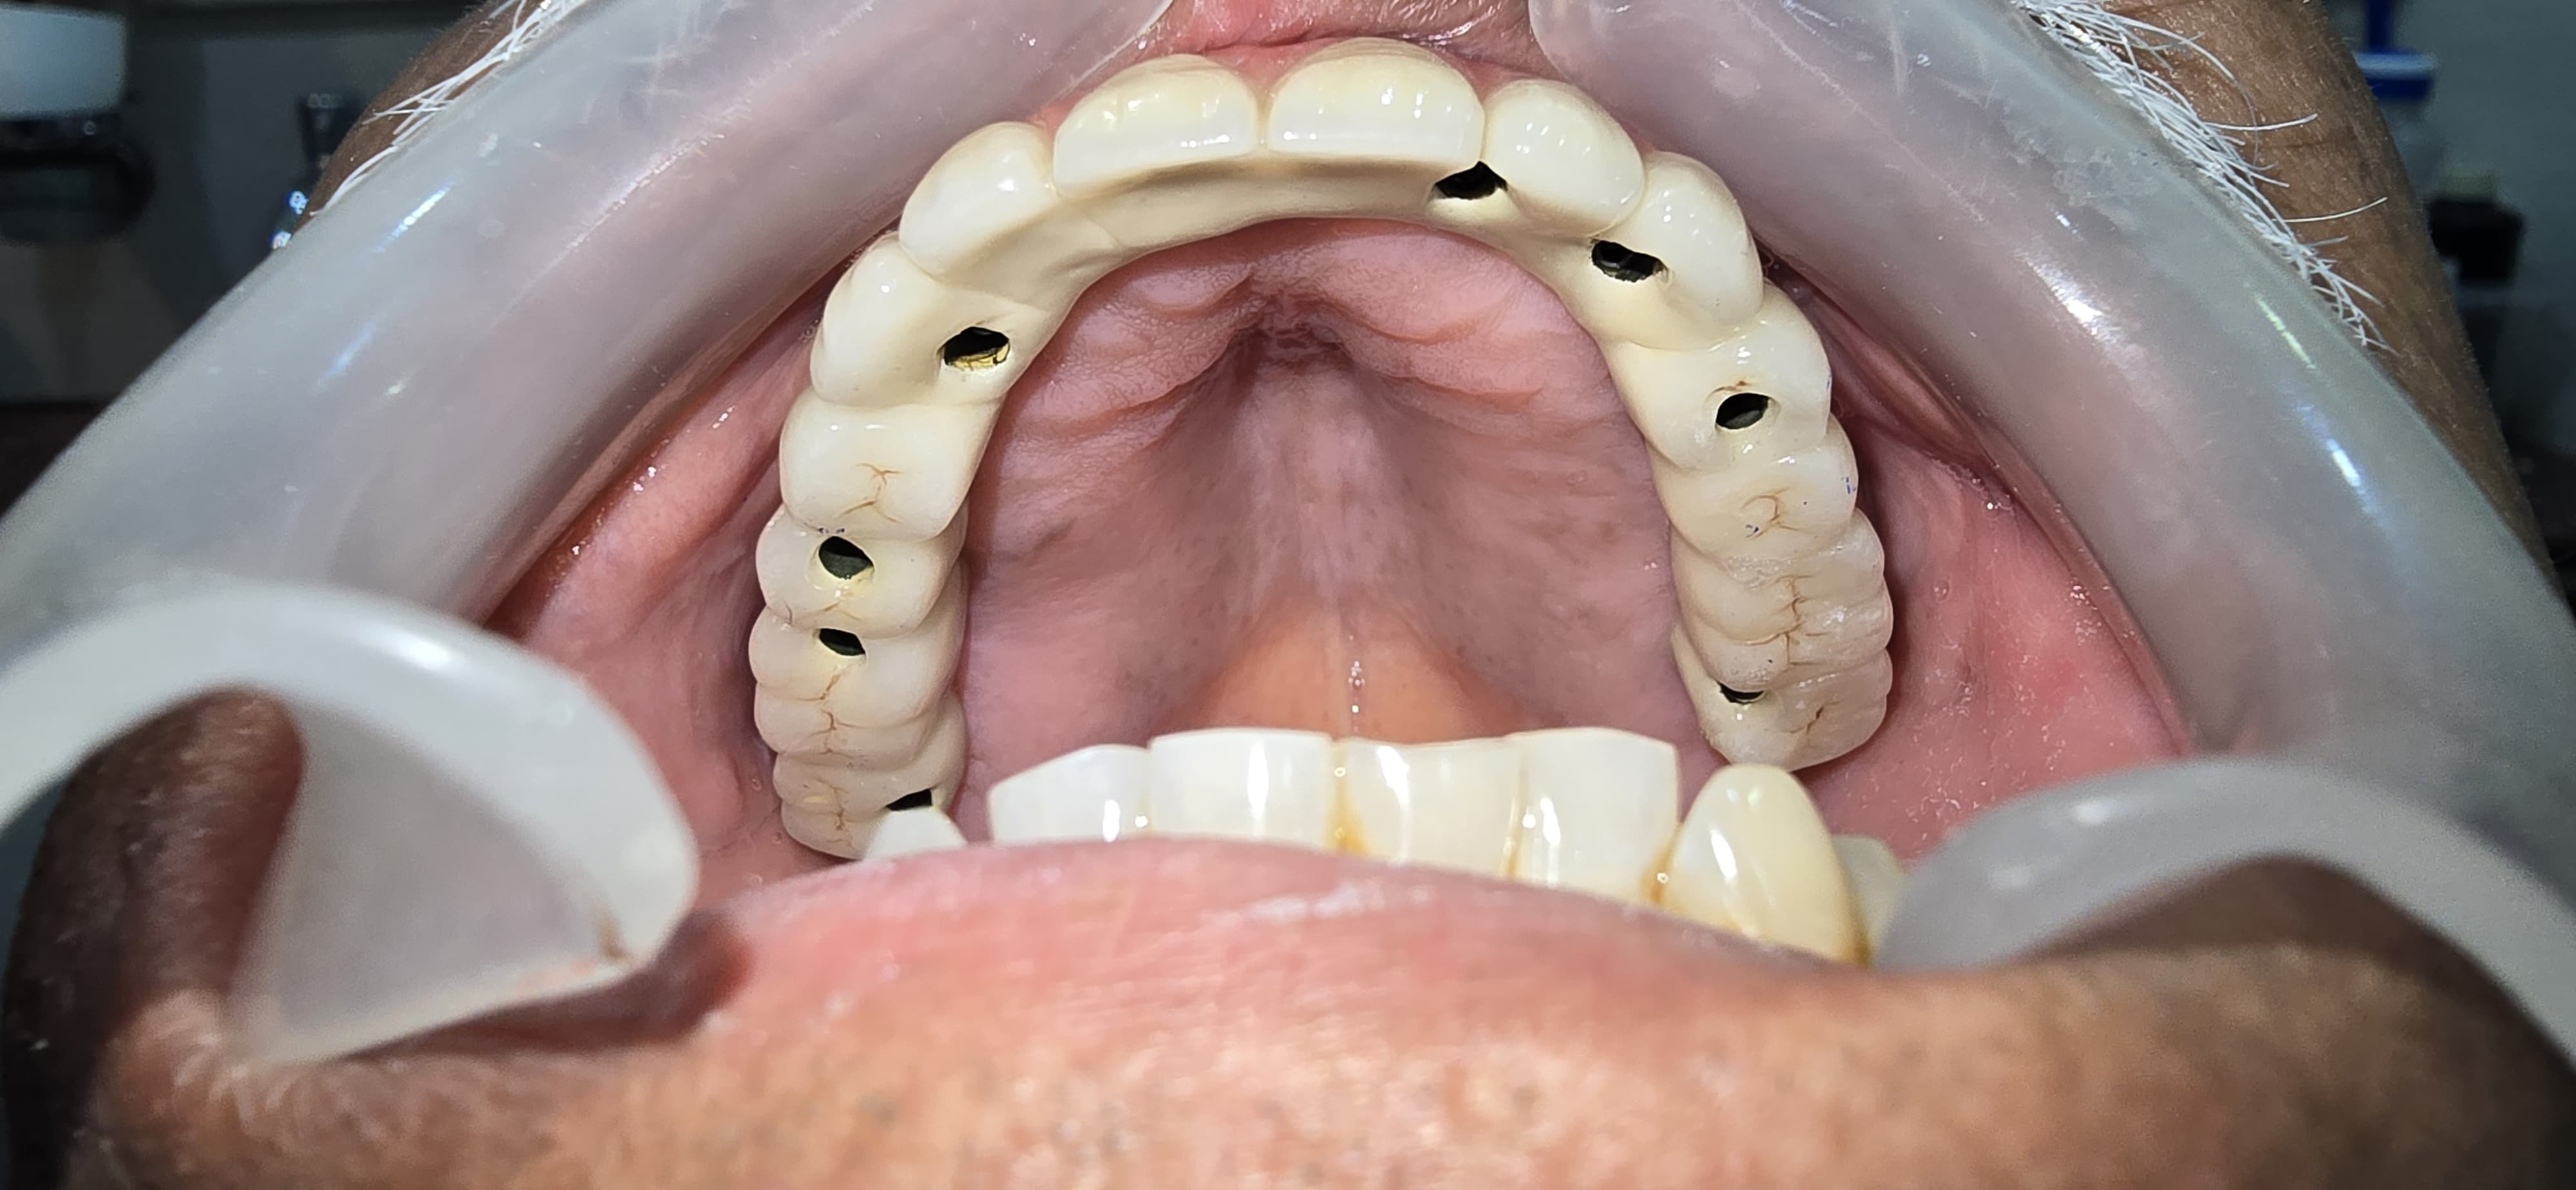

Full Mouth Implants with all Ceramic Crowns